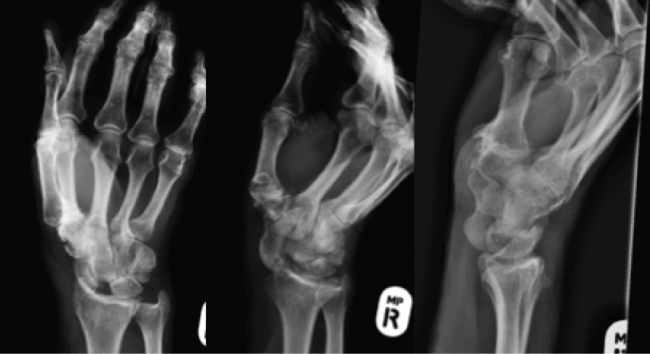

The patient was transferred promptly to the operating room. Once anesthetized a closed reduction was performed to reduce the dislocated scaphoid. Image intensifier revealed an increased scapholunate interval and no perilunar instability. A decision was then made to perform an open repair of the scapholunate ligament. A dorsal approach to the wrist with a Berger capsulotomy was performed. The Scapholunate ligament had avulsed off the scaphoid and there was a bone fragment large enough to place a 1.2 mm screw to hold the S-L ligament in addition to through bone sutures, K-wires were also used to stabilize the Scaphoid (Figure 2).

The post-operative period was complicated by a pin site infection and the development of carpal tunnel syndrome. The pin site infection was treated with oral antibiotics (cephalexin) and removal of the wires at five weeks post surgery. The patient then underwent carpal tunnel decompression at eight weeks post surgery. In this particular case acute carpal tunnel release was considered, however as the mechanism of injury was low (rare for this injury) impact, the patient had no preoperative symptoms and operative intervention was prompt it was elected not to perform this acutely. In high impact injuries carpal tunnel release should be considered especially if there are preoperative symptoms.

The patient's wrist was immobilized in a plaster for eight weeks. From week's eight to twelve the patient had a removable wrist splint, which was worn during the day but removed three times a day to begin range of motion exercises with a hand therapist. After twelve weeks formal physiotherapy continued to improve range of motion and strength of the upper limb.

At last review 12 months after the injury the patient had a pain free wrist with flexion of 50 degrees, extension of 60 degrees, pronation of 80 degrees, supination of 80 degrees. Subjectively the patient had returned to his premorbid level of function